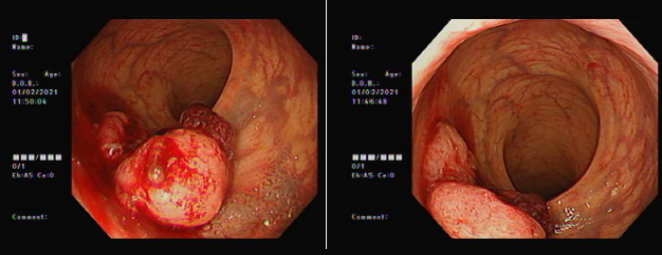

72岁的张大爷在2021年7月出现间断便血,在潞河医院预约了肠镜检查,提示直肠距肛门有一个约4-7cm肿物,活检病理提示直肠腺癌,完善检查发现合并肺内结节,考虑为直肠癌IV期,双肺转移。由于张大爷曾有20多年的高血压、冠心病史,在协和医院就诊治疗期间出现了严重的急性心梗紧急手术治疗,出院后心功能一直难以恢复正常,综合评估难以耐受直肠癌手术,甚至无法耐受单药卡培他滨化疗,因此来到了潞河医院放疗科。放疗科根据张大爷的基础情况及病情,给他制定了原发灶及转移灶的分别放射治疗方案。

肠镜检查

在治疗前,张大爷一直担心自己的身体难以坚持整个治疗周期,但在温和的放射治疗中,张大爷并未出现任何明显的不适,很愉快地配合医生一起完成了整个治疗。治疗结束后,复查治疗结果,结合影像复查对比,张大爷的原发与转移病灶均得到很好的控制,张大爷和家人看到结果后如释重负,非常感激放疗科的医务人员。张大爷感慨地说,没想到像我这样的年纪大又合并严重心脏疾病的患者也能很轻松的完成整个治疗过程,看来放疗真的是一种非常温和又安全的治疗手段。